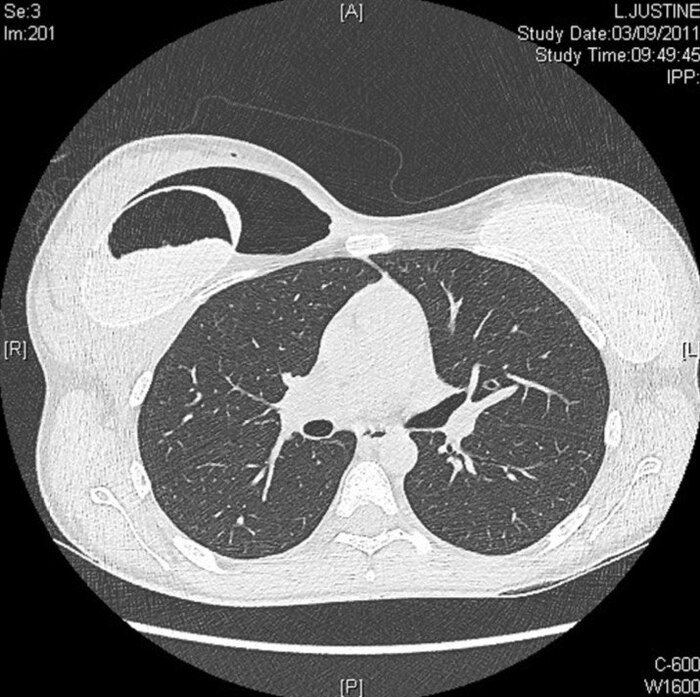

Компьютерная томография грудной клетки позволила выявить свободный газ и жидкость в ложе протеза, а также в самом протезе Фото 3.

Figure 3. Предоперационная компьютерная томография грудной клетки: отмечается наличие воздуха и жидкости в перипротезной ложбинке, а также в самом импланте.

Также определялся гетерогенный разрыв внутрипротезного силиконового геля.